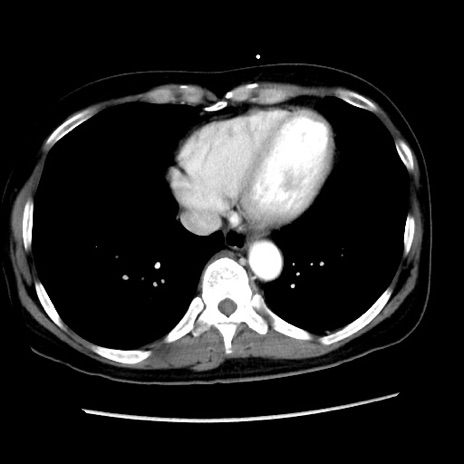

症例10(横断像)

【症例】 50歳代女性

【主訴】 腹痛

【現病歴】前日生レバーを食べた。今朝に排便あり。 昼前に突然発症の腹痛を生じ、当院救急外来を受診した。

【既往歴】 子宮筋腫にてで子宮全摘後

【身体所見】 意識清明、腹部:平坦、軟、下腹部やや左を中心に圧痛・反跳痛あり、筋性防御あり

【データ】WBC 7800、CRP 0.07